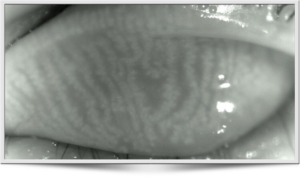

De BlephEx© behandeling is een onderdeel van de droge-ogen behandeling, de optometrist voert deze uit in ons optometrisch centrum in Hurdegaryp. Deze ooglidbehandeling verwijderd korstjes en schilfertjes zoals die bij blepharitis te zien zijn. Maar helpt ook bij het voorkomen van verstopte taglkliertjes bij meibomitis.  Wat weer heel belangrijk is bij een goede werking van de Meibom klieren en daarmee het voorkomen en verbeteren van de traanfilm bij droge ogen. Lees hier meer over deze ooglidreiniging.

Met een elektrisch aangedreven draaiend micro sponsje worden uw ooglidranden en wimpers veilig en zorgvuldig gereinigd. Daardoor kunnen de Meibom kliertjes in de oogleden gestimuleerd. Want deze klierstoffen vormen een belangrijk onderdeel van de traanfilm. De Blephex-behandeling zorgt ervoor dat korstjes, schilfers en talg worden verwijderd en het ooglid wordt voorzichtig maar effectief gepoetst. Om verspreiding van bacteriën tegen te gaan ooglid wordt elk ooglid met een nieuw sponsje gereinigd. Van deze poetsbeurt voelt u nagenoeg niets. Want de behandeling is absoluut pijnloos, hooguit misschien een wat kriebelend gevoel. Soms kan na afloop van de Blephex behandeling de traan laag nog wel wat verstoord zijn, waardoor u enkele uren nog wat wisselend kunt zien. wat extra druppel is vaak de oplossing.

Tijdens de behandeling geeft het roterende sponsje een kriebelend gevoel aan de ooglidranden. Het zicht kan na de Blephex behandeling tijdelijk wat minder zijn. Er kan wel eens een kleine irritatie aan het oogoppervlak ontstaan, maar dit herstelt zich snel, vaak binnen enkele dagen. De ooglidranden kunnen, soms ook de dag na de behandeling, nog wel wat gevoelig zijn.